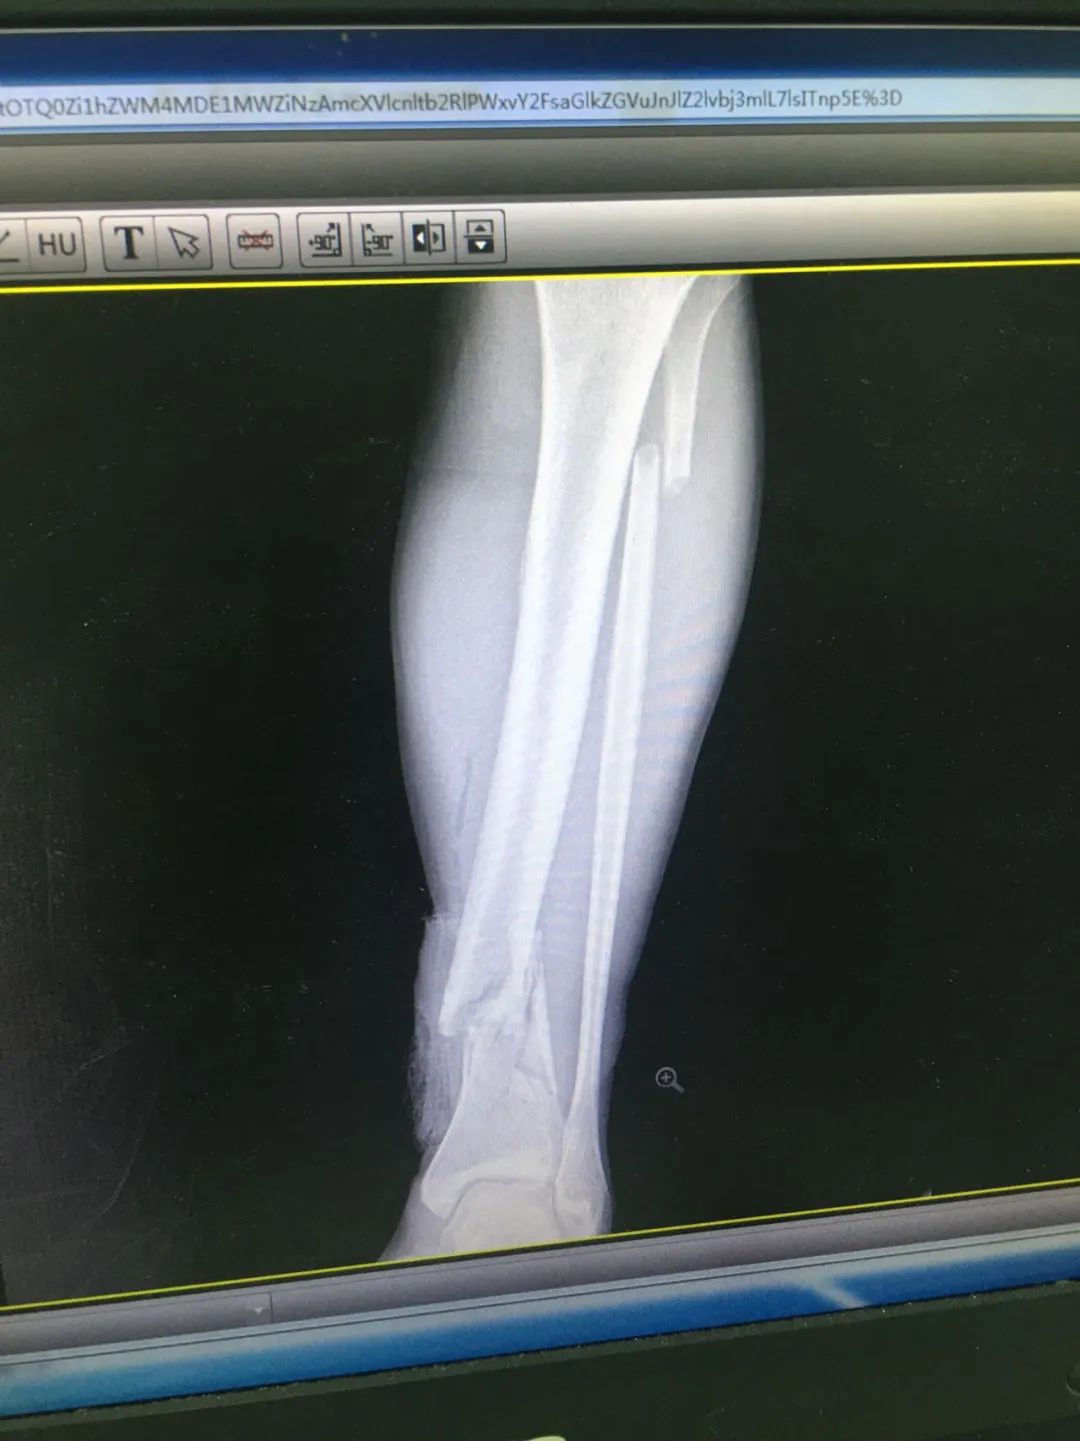

入院時(shí),劉先生已失血性休克。急診科為劉先生安排X線及CT攝片檢查,顯示左股骨干、左腓骨上端骨折,左脛骨遠(yuǎn)端粉碎性骨折,頭皮及全身多處皮膚軟組織挫裂傷,隨后收治于骨科。

骨科徐自勝醫(yī)生為劉先生仔細(xì)查體后發(fā)現(xiàn),其頭頂部偏左位置有一長(zhǎng)約3cm的傷口,深達(dá)顱骨,周?chē)醒E;左股骨中段位置畸形、腫脹,肉眼可見(jiàn)一道長(zhǎng)約5cm的傷口,有血液流出,局部壓痛陽(yáng)性;左小腿遠(yuǎn)端腫脹、畸形,也有一道2cm的傷口,左下肢活動(dòng)嚴(yán)重受限。

第1次手術(shù)10天后,骨科為劉先生安排了第2次手術(shù),歷經(jīng)3個(gè)小時(shí),成功完成左股骨干骨折及左脛骨遠(yuǎn)端骨折閉合復(fù)位內(nèi)固定術(shù),植入兩根30cm×10mm、34cm×10mm髓內(nèi)釘。

術(shù)后一周,患者手術(shù)切口愈合良好,左下肢皮膚感覺(jué)及肌力正常,左足末梢循環(huán)恢復(fù),復(fù)查X片顯示骨折復(fù)位標(biāo)準(zhǔn),內(nèi)固定物位置良好。